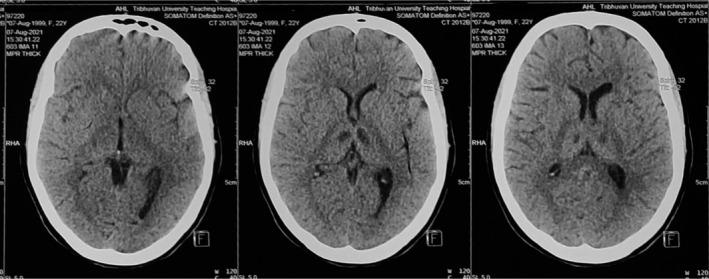

Staphylococcal endocarditis with meningitis and basal ganglia infarcts mimicking meningococcemia.

is one of the common causes of infective endocarditis (IE). IE can present with various neurological complications such as stroke, brain abscess, and meningitis, the mortality rate can be very high in such cases.

是感染性心内膜炎(IE)的常见病因之一。IE可伴有各种神经系统并发症,如中风、脑脓肿和脑膜炎,在这种情况下死亡率可能非常高。